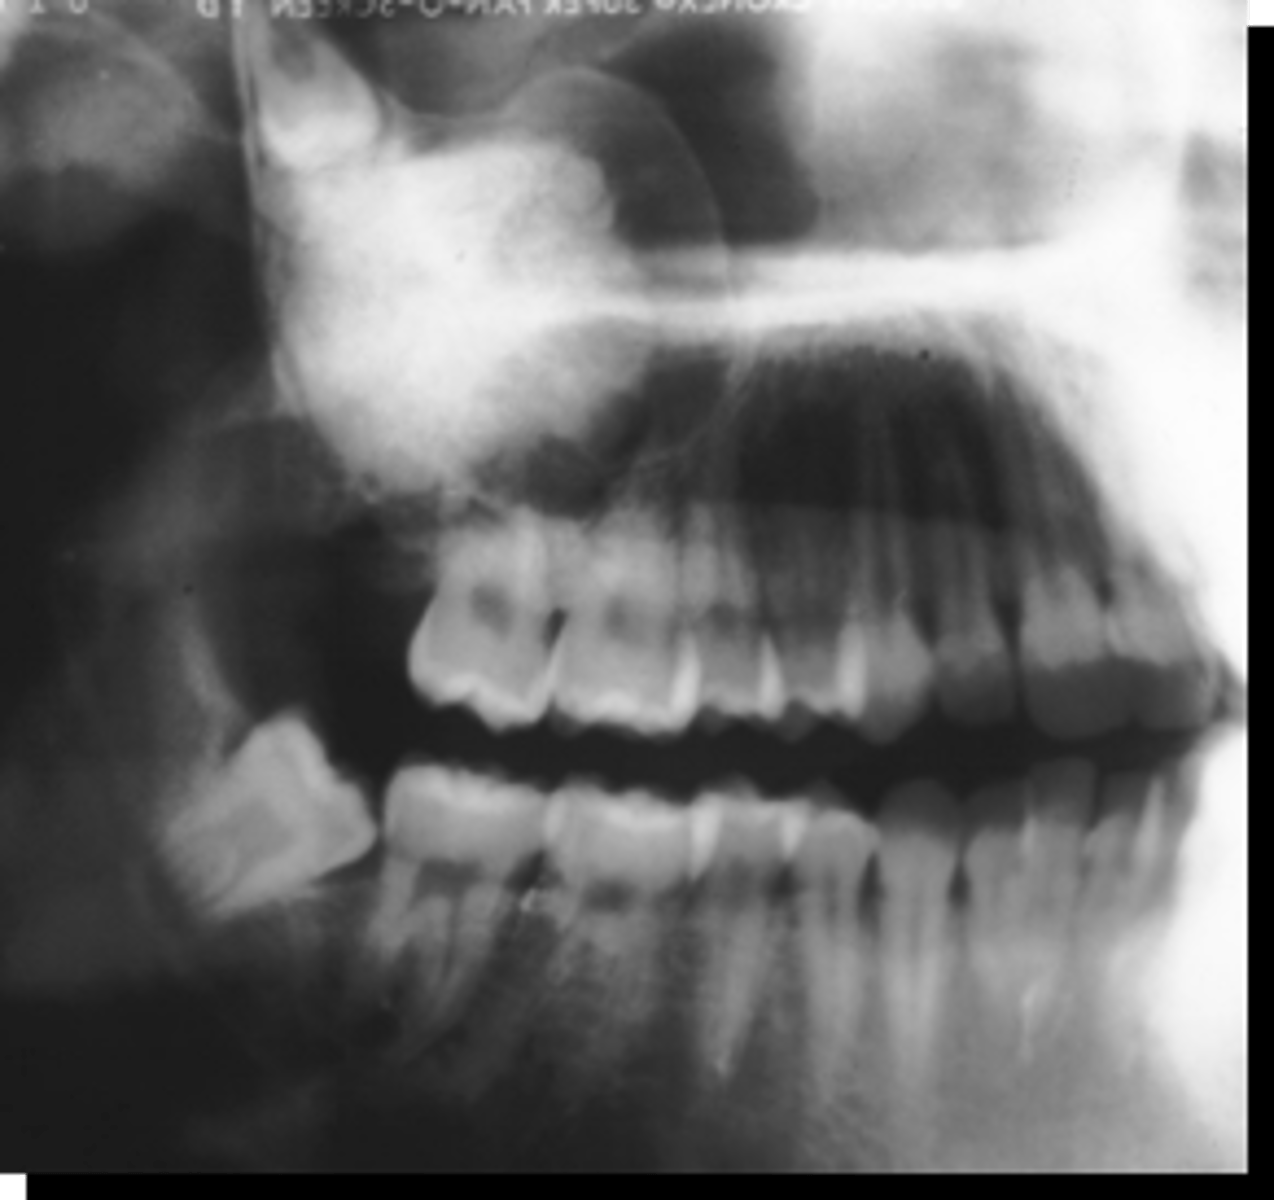

what is the most common location of an Ameloblastoma?

40 y/o patient presents with a well defined, corticated, multi-locular with thick/coarse curved septae lesion on the posterior mandible. Thinning and expansion of the border of the mandible is evident and it displaces the IAN inferiorly. The roots of tooth #30 are resorbed. The lesion is VERY expansile. What is the diagnosis?

Ameloblastoma

KOT

40 y/o patient presents with a well defined, corticated, multi-locular with thick/coarse curved septae lesion on the posterior mandible. Thinning and expansion of the border of the mandible is evident and it displaces the IAN inferiorly. The roots of tooth #30 are resorbed. What pathologies are included in your differential diagnosis?

40 y/o patient presents with a well defined, corticated, uni-locular, peri-coronal lesion that displaces #32 on the posterior mandible. Thinning and expansion of the border of the mandible is evident and it displaces the IAN inferiorly. What pathologies are included in your differential diagnosis?

40 y/o patient presents with a well defined, corticated, multi-locular with thick/coarse curved septae lesion on the posterior mandible. Thinning and expansion of the border of the mandible is evident and it displaces the IAN inferiorly. The roots of the surrounding teeth are displaced. The lesion is VERY expansile. What is the diagnosis?